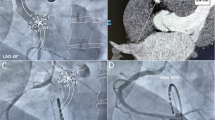

Cryoballoon ablation

Ablation was performed in patients under procedural sedation and analgesia with midazolam and pethidine. A temperature probe was routinely placed in the esophagus to monitor temperature changes during the freezing cycles. Access for the PVI was obtained through the right femoral vein. A diagnostic multipolar catheter was inserted and positioned in the coronary sinus (CS) via central venous access. Single transseptal puncture was performed using fluoroscopic guidance, employing the Brockenbrough technique, and the steerable 15 F sheath (Flexcath™, Medtronic, USA, or Polarsheath™, Boston Scientific, USA) was introduced under fluoroscopic guidance into the LA. Subsequently, the AFA-Pro CB or POLARx CB were inserted and carefully positioned proximal to the PV ostium. After inflation, the devices were advanced and pushed to the ostium to occlude it completely. Optimal and effective occlusion of the PVs was verified by contrast application. To maximize TTI recordings, the spiral mapping catheter (Achieve™, Medtronic, USA, or Polarmap™, Boston Scientific, USA) was retracted as close as possible to the PV ostium without compromising PV occlusion.

The freezing process was typically set for 240 s. Adjustments were possible based on TTI, temperature changes, minimal temperature, esophageal temperature, and others. Criteria for premature termination were a freezing temperature of − 70 °C for POLARx (mandatory technical parameter of CB system), an esophageal temperature below 16 °C, or attenuation of phrenic nerve capture.

While performing the ablation procedure on the right PVs, the function of the phrenic nerve was observed through continuous phrenic nerve pacing using a diagnostic catheter positioned in the superior vena cava. Diaphragmatic excursion was assessed by continuous abdomen palpation by the investigator and intermittent fluoroscopy, with immediate interruption of ablation on detection of attenuated diaphragmatic movements. Additionally, in the POLARx group, the newly introduced diaphragm movement sensor (DMS) from Boston was used to monitor the function of the phrenic nerve. To verify ablation success, the spiral mapping catheter was re-advanced in the targeted PVs. Elimination of all PV potentials was defined as entrance block. Exit block was evaluated by electrical stimulation within each PV.